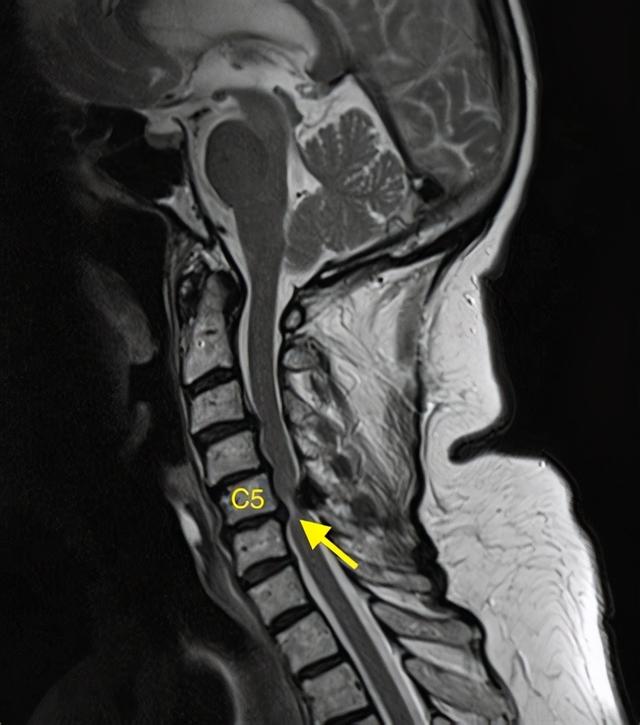

而脊髓型颈椎病就不一样了 , 因为颈椎突出和压迫的部位是脊髓 , 也就是最重要的神经中枢 , 所以严重程度会更大一些 。

最严重的脊髓型颈椎病可能会出现大小便失禁 , 甚至瘫痪的结局 。

但是脊髓型颈椎病可就不一样了 , 这可是颈椎病中的特殊类型 , 如果在没有确定颈椎病类型的时候 , 就是用外力 , 很有可能出现颈椎脊髓损伤 。

特别是在一些不规范的按摩场所 , 手法往往很暴力 , 在没有确定疾病原因的时候 , 可能导致颈椎椎体脱位 , 也可能出现脊髓损伤加重 。

脊髓损伤了会怎么样?

相信你一定听过 , 但是在这里重申一遍 , 脊髓损伤之后是不可恢复的 , 容易出现瘫痪 。